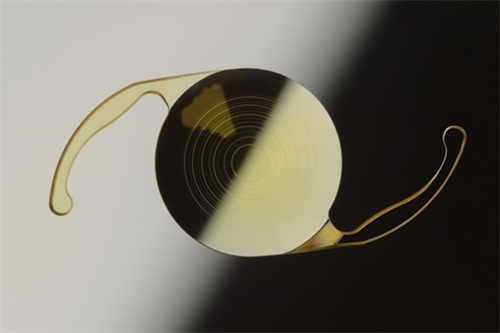

白内障手术是一种非常常见且安心的眼科手术,通常采用超声乳化技术将模糊的晶状体取出,然后植入人工晶状体以改善眼部视力。